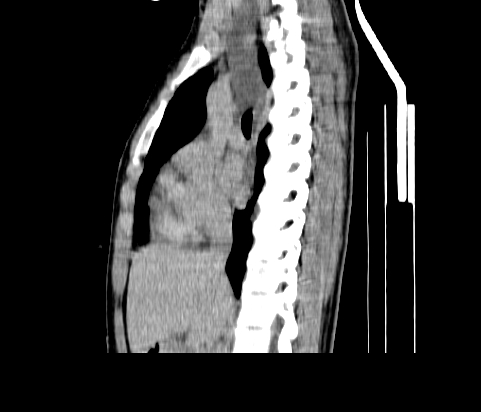

胸部

重建